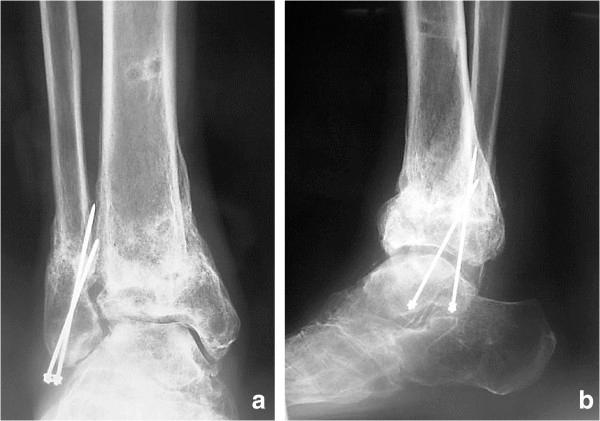

A 53-year-old Japanese man fractured his right ankle. The fractured ankle was treated nonsurgically with a plaster cast. Although he remained non-weight-bearing for 3 months, radiography at 3 months showed nonunion. The nonunion was treated by Ilizarov external fixation of the ankle. The external fixator was removed 99 days postoperatively, at which time the patient exhibited anatomical and functional recovery and was able to walk without severe complications.

In patients with diabetes mellitus, severe nonunion of ankle fractures with Charcot arthropathy in which the fracture fragment diameter is very small and the use of internal fixation is difficult is a clinical challenge. Ilizarov external fixation allows suitable fixation to be achieved using multiple Ilizarov wires.